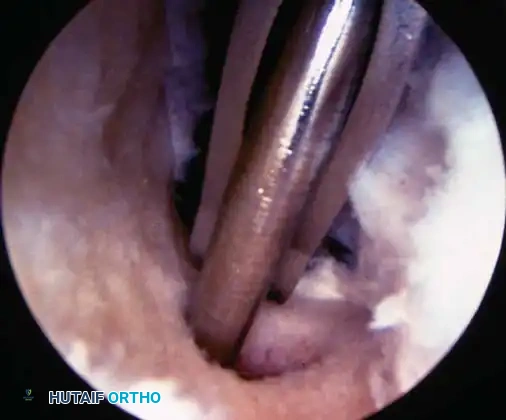

Resection of Bucket-Handle Tear TECHNIQUE 48-1

• For reduction of the meniscal fragment, use a probe or a blunt trocar to reduce the fragment to its normal position.

• Begin the technique (Fig. 48-19A) with partial division of the posterior attachment of the meniscal fragment. This can be done with basket forceps, scissors, or an arthroscopic knife. Attempt to cut almost completely through the posterior attachment of the mobile fragment at its junction with the remaining normal meniscal rim (Fig. 48-19B). This cut should not be done blindly to prevent harm to the normal meniscus or articular cartilage or both. Exposure can be aided by passing the arthroscope through the intercondylar notch to look down onto the posterior horn of the meniscus while cutting, or a posteromedial portal can be made if necessary to look directly down onto the meniscus for visualization or to pass through the posterior compartment for cutting of the meniscus.

• Leave a small tag of meniscal tissue intact posteriorly to prevent the meniscus from fl oating freely in the posterior compartment after anterior release.

• Divide the anterior horn attachment with angled scissors, basket forceps, or an arthroscopic knife. Make the release of the anterior attachment fl ush with the intact anterior rim so that no stump or “dog ear” remains (Fig. 48-19C). If the approach is diffi cult from the ipsilateral portal, changing portal sites and approaching from the contralateral portal with the operating instrument often facilitates making this cut. Rarely, a midpatellar portal is necessary so that both anterior portals can be used for instrumentation.

• Use a hemostat to dilate the capsular incision before attempting meniscal removal.

• Insert a grasping clamp through the ipsilateral portal, and grasp the meniscal fragment as close to its remaining posterior attachment as possible. Keep the meniscal fragment in view, and twist and rotate the grasping forceps at least two revolutions while applying traction to avulse the small bridge previously created.

• If the meniscal fragment does not come loose as planned, use a grasper through the lateral portal for traction on the meniscus, and pass arthroscopic scissors through the same portal to complete the resection posteriorly. If it is still diffi cult with this technique, make an accessory portal, 1 cm from the anterior portal using the spinal needle. The other option is to make an accessory midpatellar portal for the arthroscope and use the two anterior portals for instrumentation.

• Observe the fragment as it exits the joint to ensure complete removal (Fig. 48-19D).

• Occasionally, the fragment is so large that it lodges within the subcutaneous tissues. In these circumstances, the skin incision may have to be enlarged to deliver the fragment. Additional longitudinal tears can be treated as previously described.

• If there are no further tears, use a motorized meniscal shaver to smooth the remaining rim.

• Before the procedure is completed, examine the posterior compartment with either a 30or 70-degree arthroscope inserted through the intercondylar notch or a 30-degree oblique arthroscope inserted through the corresponding posterior portal.